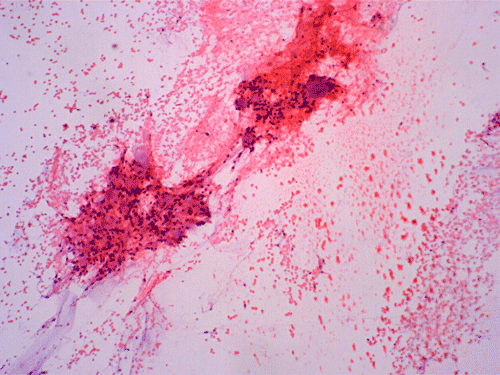

Clinical informationThe patient was a 40 year-old man with back pain for a long but unknown duration of time. MRI revealed a sharply circumscribed, lobulated, brightly enhancing, 3 cm mass in the cauda equina. The mass was removed and the followings are representative photomicrographs from the specimen. Panel A to C are taken from intraoperative cytologic preparation, D and E are taken from frozen section, F to H are taken from permanent sections.

On cytologic preparations, there are clumps of tissue that do not smear out well (Panel A). On higher magnification, these tissue clusters are composed of large blobs of bluish, acellular, mucoid material admixed with cells with relatively uniform, bland nuclei and small amount of cytoplasm (Panel B). In the less tightly packed areas, the long cytoplasmic processes of the cells can be well appreciated (Panel C). These long processes are highly suggestive of a glial neoplasm. On frozen sections, the lesion is composed of multiple blobs of bluish, mucoid material surrounded by tumor cells (Panel D and E). Features of the paraffin sections are not that much different from that of the frozen sections (Panel F G H).